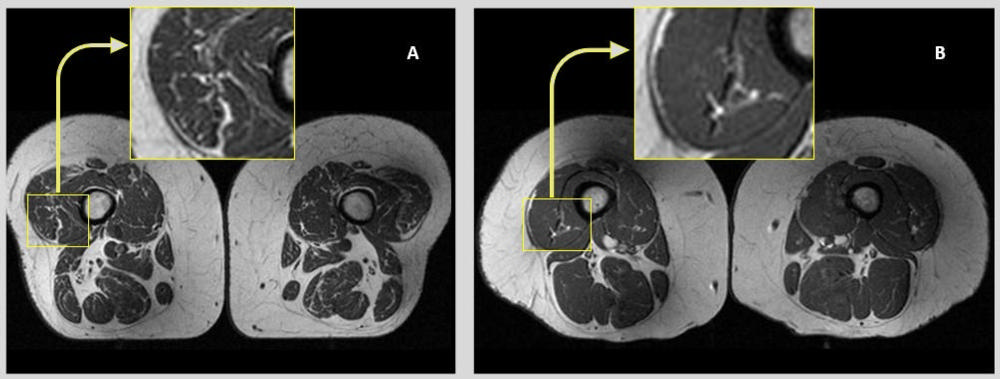

Figure 1. Axial T1-weighted bilateral thigh MR images and magnified frames providing a closer look at the areas in lateral aspects of quadriceps femoris muscles (knee extensors) from two obese, female participants, aged 58 (A) and 62 years (B), respectively. In A, the thigh muscles on both sides demonstrate abundant fatty streaks, consistent with a high Goutallier grade of 45 for this participant, whose diet from the past 12 months consisted 68% of ultra-processed foods. In B, the thigh muscles show fewer fatty streaks as highlighted in the magnified image, consistent with a low Goutallier grade of 17 for this participant, whose diet contained only 36% ultra-processed foods.